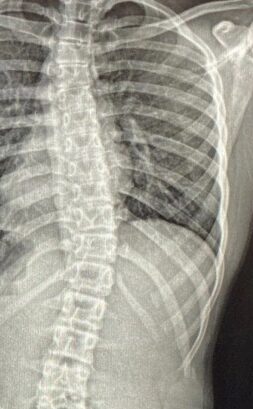

يُعتبر اعوجاج العمود الفقري (Scoliosis) من أكثر الاضطرابات شيوعًا بين الأطفال والمراهقين، ويتميز بانحناء جانبي للعمود الفقري مصحوب غالبًا بدرجة من الالتفاف أو الدوران الفقري (Axial Rotation). هذا الدوران يجعل العمود الفقري لا ينحني فقط إلى الجنب، بل أيضًا يلتف حول نفسه، مما يسبب تغيرًا في شكل الصدر والكتفين.

عند الإصابة باعوجاج العمود الفقري، لا يقتصر الأمر على ميل جانبي بسيط، بل يحدث غالبًا التفاف للفقرات حول محورها الطولي، فيدور الجزء الأمامي من الفقرة (الجسم الفقري) في اتجاه، بينما تدور العمليات الشوكية في الاتجاه المعاكس.

هذا الالتفاف يجعل أحد جانبي الصدر يبرز أكثر من الآخر، وهو ما يُلاحظ عادة عند انحناء الطفل إلى الأمام أثناء الفحص، حيث يظهر بروز في جانب الظهر.

اعتمد الأطباء على طريقة شعاعية دقيقة لقياس دوران الفقرات باستخدام الأشعة السينية (X-ray).

الطريقة تعتمد على ملاحظة موقع ظل النتوءات العظمية للفقرات (Pedicles) في الصورة الشعاعية.

عندما تكون الفقرة في وضعها الطبيعي، تظهر النتوءات الجانبية (Pedicles) على جانبي الجسم الفقري بشكل متساوٍ.

أما عندما تدور الفقرة، فإن أحد النتوءين يقترب من منتصف الجسم الفقري بينما يختفي الآخر جزئيًا.

من خلال قياس مقدار انزياح هذه النتوءات عن المركز، يمكن للطبيب حساب درجة الدوران باستخدام معادلة رياضية بسيطة تم التحقق من دقتها سريريًا.

هذه الطريقة تتيح للطبيب تقدير زاوية الدوران بالدرجات من خلال صورة واحدة فقط، دون الحاجة إلى تصوير مقطعي أو ثلاثي الأبعاد.